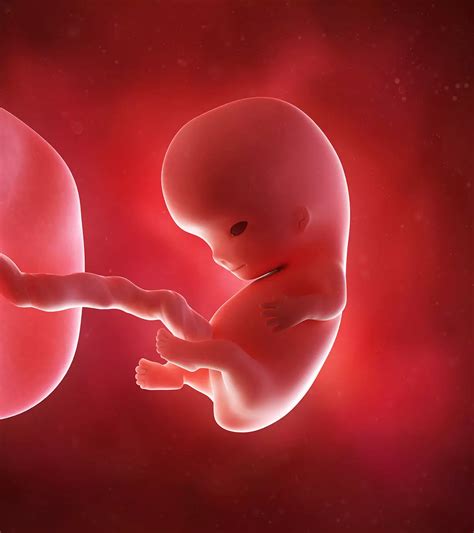

• baby at 8 weeks gestation

• 8 weeks pregnant baby development

• baby 8 weeks pregnant pictures